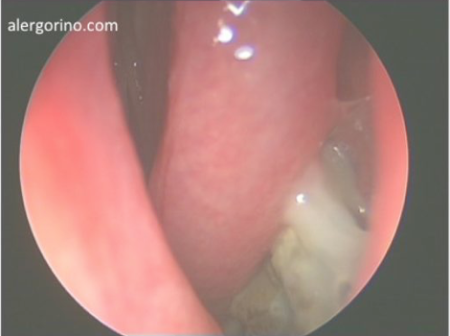

El diagnóstico se realiza mediante la historia clínica y una endoscopia nasal que proporcionan datos como la presencia de pólipos, la descarga mucopurulenta y el edema o la obstrucción de las áreas de drenaje de los senos paranasales. Si no se produjera una respuesta al tratamiento médico se evalua la situación de los senos paranasales mediante una tomografía computarizada (TC).